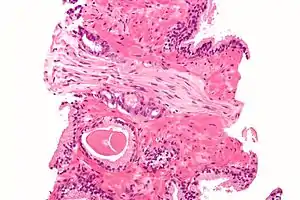

Histopathologic diagnosis

A histopathologic diagnosis mainly includes assessment of whether a cancer exists, as well as any subdiagnosis, if possible. Histopathologic subdiagnosis has implications for the possibility and methodology of Gleason scoring.[85] The most common histopathological subdiagnosis is acinar adenocarcinoma, constituting 93% of diagnoses.[86] The most common form of acinar adenocarcinoma, in turn, is "adenocarcinoma, not otherwise specified", also termed conventional, or usual acinar adenocarcinoma.[87]

After a biopsy, a pathologist examines the samples under a microscope. If cancer is present, the pathologist reports the grade of the tumor. The grade tells how much the tumor tissue differs from normal prostate tissue and suggests how fast the tumor is likely to grow. The pathologist assigns a Gleason number from 1 to 5 for the most common pattern observed under the microscope, then does the same for the second-most common pattern. The sum of these two numbers is the Gleason score. The Whitmore-Jewett stage is another method.